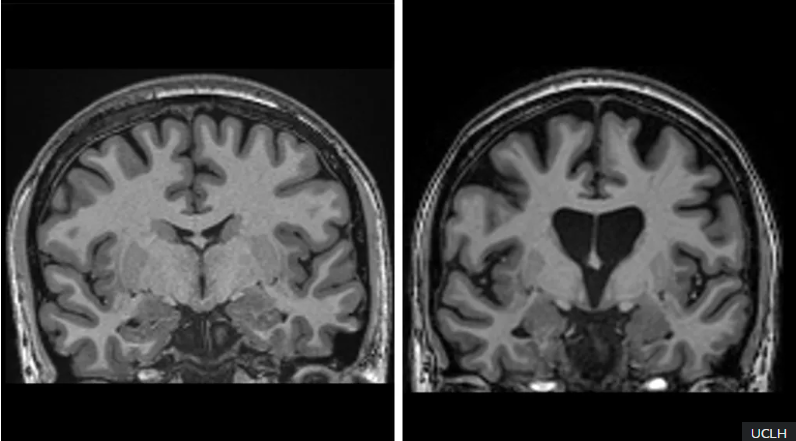

პროცედურა ტვინში ხელოვნურად შემუშავებული ვირუსის შეყვანით იწყება, რომელიც სპეციალურად შემუშავებული დნმ-ის თანმიმდევრობას შეიცავს. რეალურ დროში მრტ სკანირების ფონზე ,აღნიშნული ვირუსი მიკროკათეტერის საშუალებით ტვინის პუტამენსა და კუდოვან ბირთვს აღწევს და ერთგვარ “მიკროსკოპული ფოსტალიონის“ როლს ასრულებს, ტვინის უჯრედებს ახლი დნმ -ს ფრაგმენტებით ამარაგებს. რის შედეგად უკვე თავად ეს უჯრედები იწყებენ იმ გენეტიკური მასალის (რნმ) წარმოქმნას ,რომლებიც ბლოკავენ პათოგენური ცილის წარმომქმნელ ინსტრუქციებს (ე. წ. მესენჯერ რნმ-ებს) და ამით ტვინში მუტირებული ცილის დონის ამცირებენ.

29 პაციენტზე ჩატარებული კვლევის შედეგები, რომლებიც კომპანია uniQure-მ გამოაქვეყნა აჩვენებს, რომ ოპერაციიდან სამი წლის შემდეგ დაავადების პროგრესირება საშუალოდ 75%-ით შენელდა.